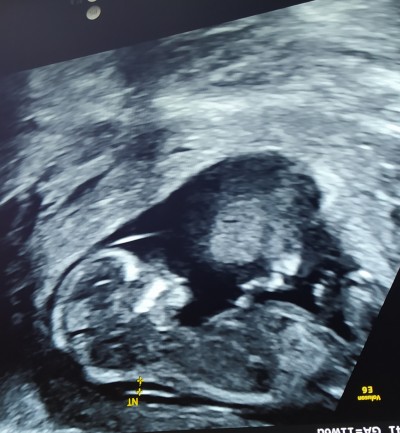

Arkadaşlar iki tane bebek görüyorum bebeğin eşi olma ihtimali var mı 15+3 haftalık İnternetten ultrason resimlerine baktım fakat böyle bişeye rastlamadım hiç

Gebelik haftası 15+3

Kordonu ile alakalı bir şey heralde

Muhtemelen plasenta o iki bebek olsa doktorunuz söylerdi ki‍♀️

Bebek olsa doktor derdi  ve o bebeğe hiç benzemiyor. O gördüğün plesenta